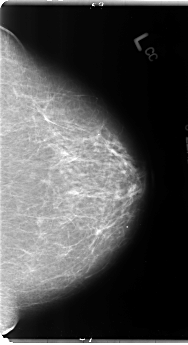

B_3106_1.RIGHT_CC

B_3106_1.LEFT_CC

LEFT_CC LINES 4824 PIXELS_PER_LINE 2624 BITS_PER_PIXEL 12 RESOLUTION 50 NON_OVERLAY

LEFT_MLO LINES 4784 PIXELS_PER_LINE 2832 BITS_PER_PIXEL 12 RESOLUTION 50 NON_OVERLAY